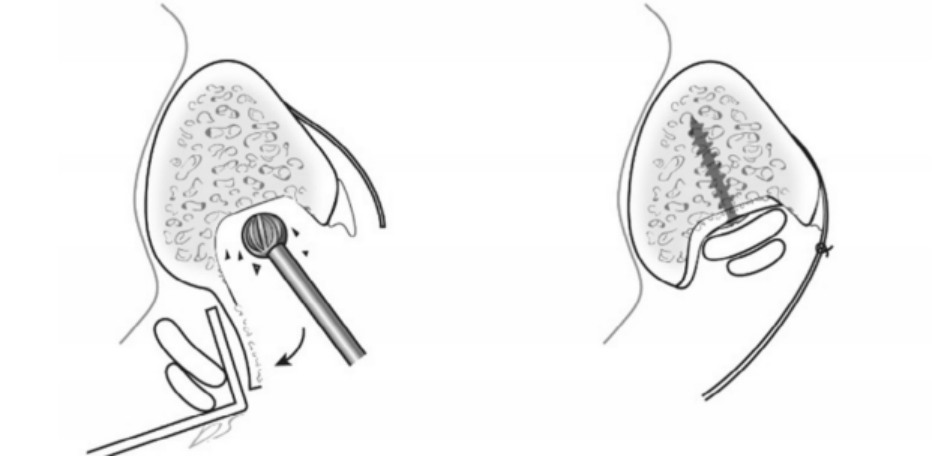

通过切除腓骨后方部分骨质,可以加深腓骨沟,改变、并增加了腓骨肌腱的稳定。

内镜下腓骨沟加深手术

11.Suh, Jae Wan; Lee, Jin Woo; Park, Jun Young; Choi, Woo Jin; Han, Seung Hwan (2017). Posterior Fibular Groove Deepening Procedure With Low-Profile Screw Fixation of Fibrocartilaginous Flap for Chronic Peroneal Tendon Dislocation. The Journal of Foot and Ankle Surgery, (), S1067251617306348–. doi:10.1053/j.jfas.2017.10.033